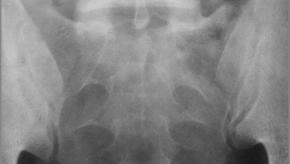

Read ArticleTaltz Shines in Non-Radiographic Axial Spondyloarthritis

Ixekizumab (IXE), an interleukin-17A (IL-17A) inhibitor, was recently approved for use in ankylosing spondylitis (also known as radiographic axial spondyloarthritis- axSpA).